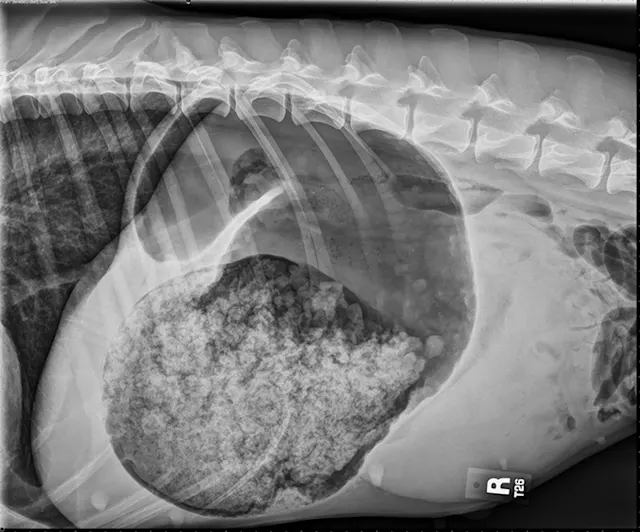

The classic double bubble appearance of GDV in the right-lateral view represents a gas-distended gastric lumen with the pylorus located craniodorsal to the fundus. Pylorus and fundus are divided by a soft tissue opaque band that compartmentalizes the gas in the fundus and pylorus, making 2 bubble shapes (Figure 1). Focal gas opacities in the gastric walls may suggest necrosis, and free gas in the abdomen can indicate gastric perforation.15

FIGURE 1

The classic double bubble appearance of GDV in the right-lateral view. Distended fundus separated from the gas-distended pylorus by a soft tissue opaque band can be noted.